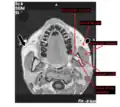

Masseter

The left masseter muscle (red highlight), partially covered by superficial muscles such as the platysma muscle (below) and both the zygomaticus major and minor muscles